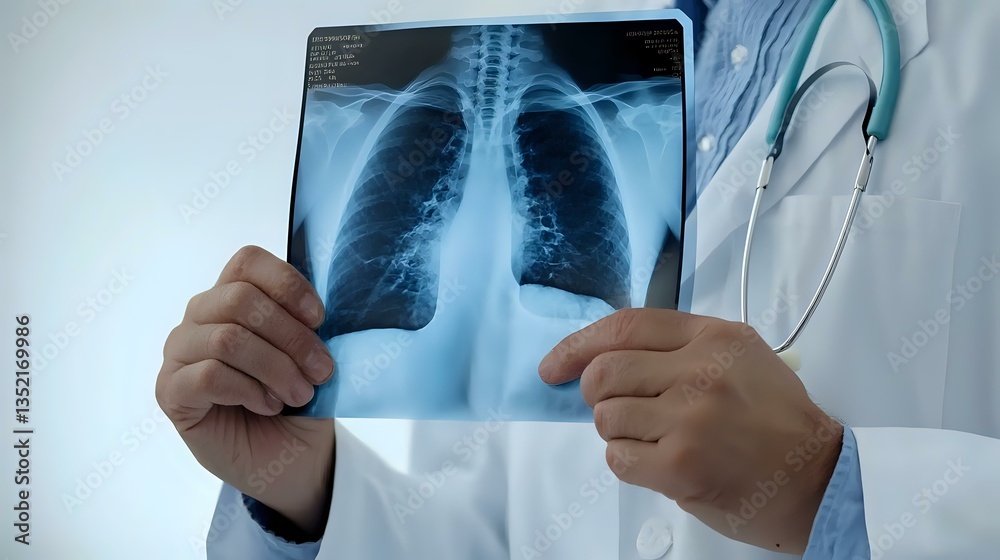

Medical professional examining chest x-ray scan showing lungs and ribcage, wearing white coat with stethoscope. Healthcare diagnostics in modern hospital setting.

Obraz drukowany na płótnie - Medical professional examining chest x-ray scan showing lungs and ribcage, wearing white coat with stethoscope. Healthcare diagnostics in modern hospital setting.

specyfikacja: Medical professional examining chest x-ray scan showing lungs and ribcage, wearing white coat with stethoscope. Healthcare diagnostics in modern hospital setting.

NazwaMedical professional examining chest x-ray scan showing lungs and ribcage, wearing white coat with stethoscope. Healthcare diagnostics in modern hospital setting.

Sprawdź wizualizacje dla obrazu Medical professional examining chest x-ray scan showing lungs and ribcage, wearing white coat with stethoscope. Healthcare diagnostics in modern hospital setting. drukowanym na płótnie. Przedstawiamy kilka wizualizacji wydruku w różej aranżacji oraz kolortyce ścian. Wizualizacje uwzględniają wydruk całego pliku, dokładny kadr i rozmiar możesz wybrać podczas konfigurowania obrazu na górze strony.